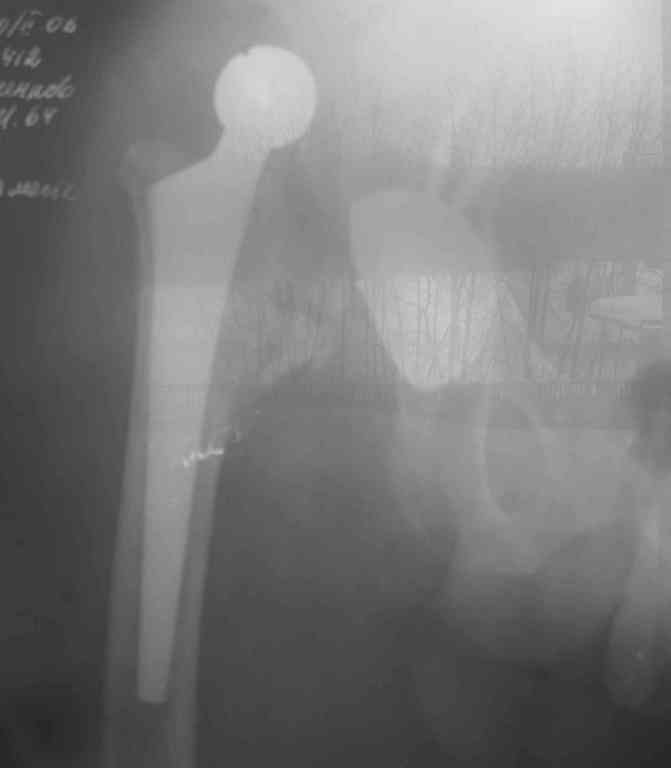

Интересный пример: (см фото)

Вывих эндопротеза на 5 сутки после операции. (причина- ошибки предоперационного планирования и интраоперационные ошибки)

Пациент от ревизии отказался.

Сейчас прошло 4 года после операции. Больной ходит с полной нагрузкой на оперированную конечность с тростью. болей нет.